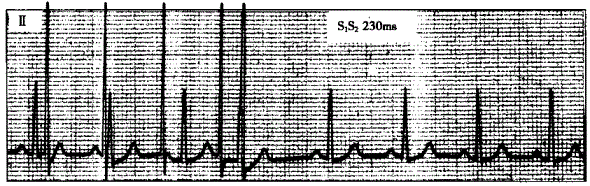

问题 心动过速诱发窗口的测定一般采用期前刺激法,即采用步长10ms进行反扫描和正扫描,并诱发心动过速,如下图显示的心动过速的诱发窗口为

选项 A.<240ms B.>230ms C.>340ms D.230~350ms E.240~340ms

答案 E

解析 :诱发窗口是指SS程序刺激进行反扫描或正扫描时,能诱发出室上性心动过速的SS刺激联律间期的宽度。在上图中,反扫描时,SS联律间期为340ms时诱发出心动过速;正扫描时,SS联律间期为240ms时诱发出心动过速;诱发出心动过速的SS联律间期介于240~340ms之间,因此诱发窗口为240~340ms。